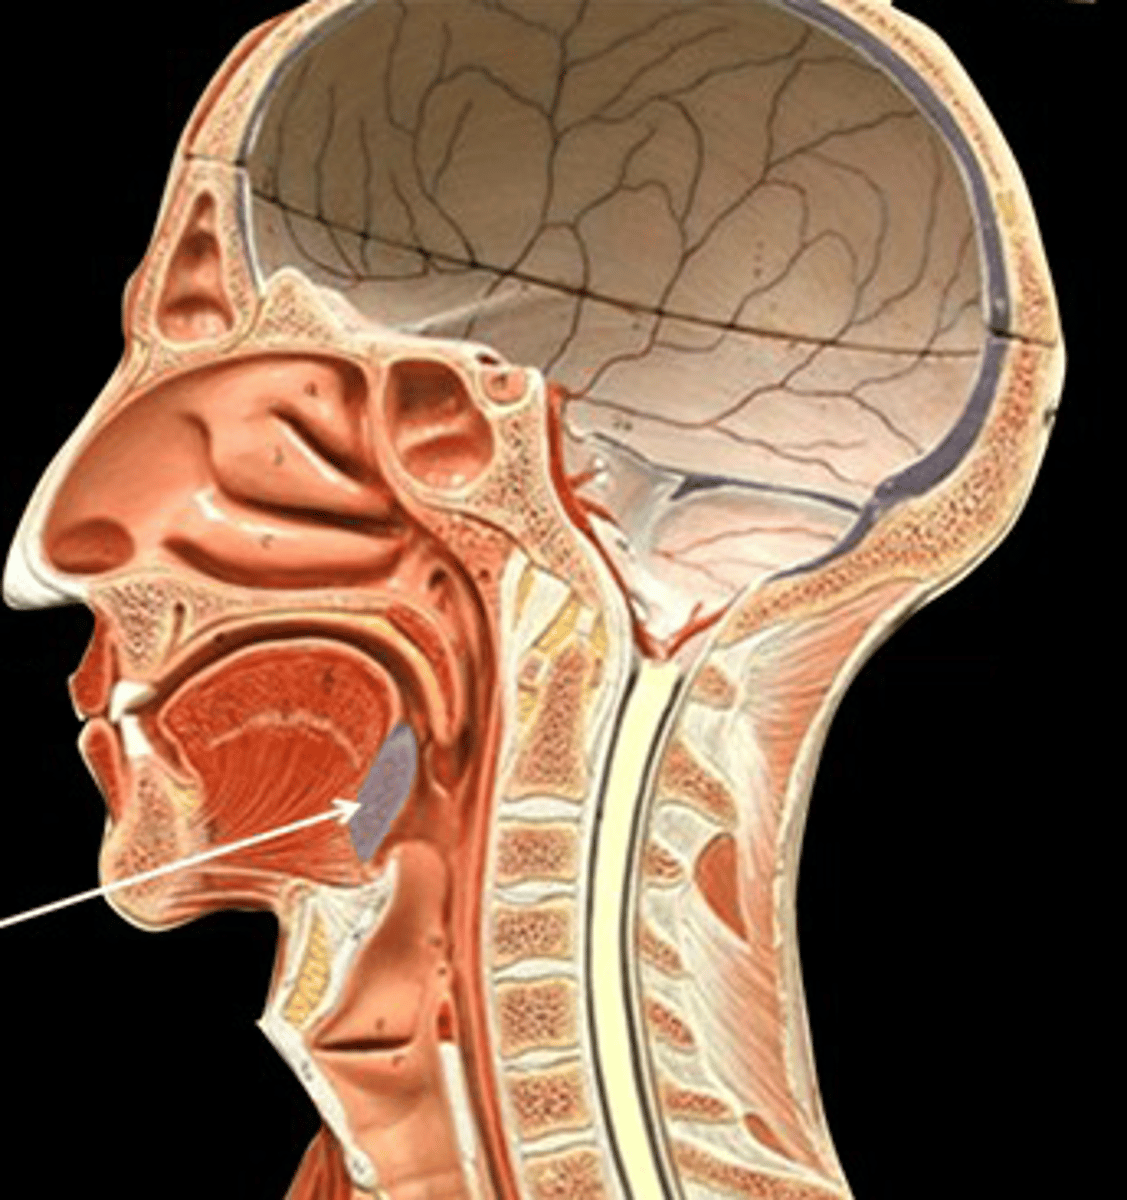

tonsils

form a ring of lymphatic tissue around the openings to the pharynx.

pharyngeal tonsils (adenoids)

sits on the posterior wall of the superior pharynx. This location allows it to filter inhaled air for pathogens.

palatine tonsils

are found on the lateral walls of the oral portion of the pharynx (the oropharynx). These tonsils are in prime position to "catch" pathogens being ingested with food.

lingual tonsils

reside on the superior surface of the posterior tongue. These tonsils are in prime position to "catch" pathogens being infested with food.

tonsillar crypts

contains lymphocytes and bacteria. Deep to the epithelium and adjacent to the crypts you can see dense lymphatic tissue

tonsillar capsule

made of dense connective tissue. It separates the tonsil from the subjacent tissues. Helps prevent the spread of infection.

Tonsillectomies used to be a common occurrence as a means of dealing with tonsil infections. Such surgeries are no longer performed as often. Why do you suppose this is?

Tonsillectomies remove one of the first lines of defense against inhaled and ingested pathogens.